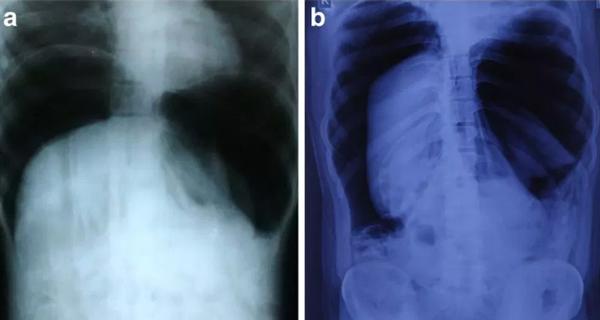

Hình chụp X-quang bụng cho thấy không khí bên trong bụng của người đàn ông 24 tuổi bị thương do tai nạn.